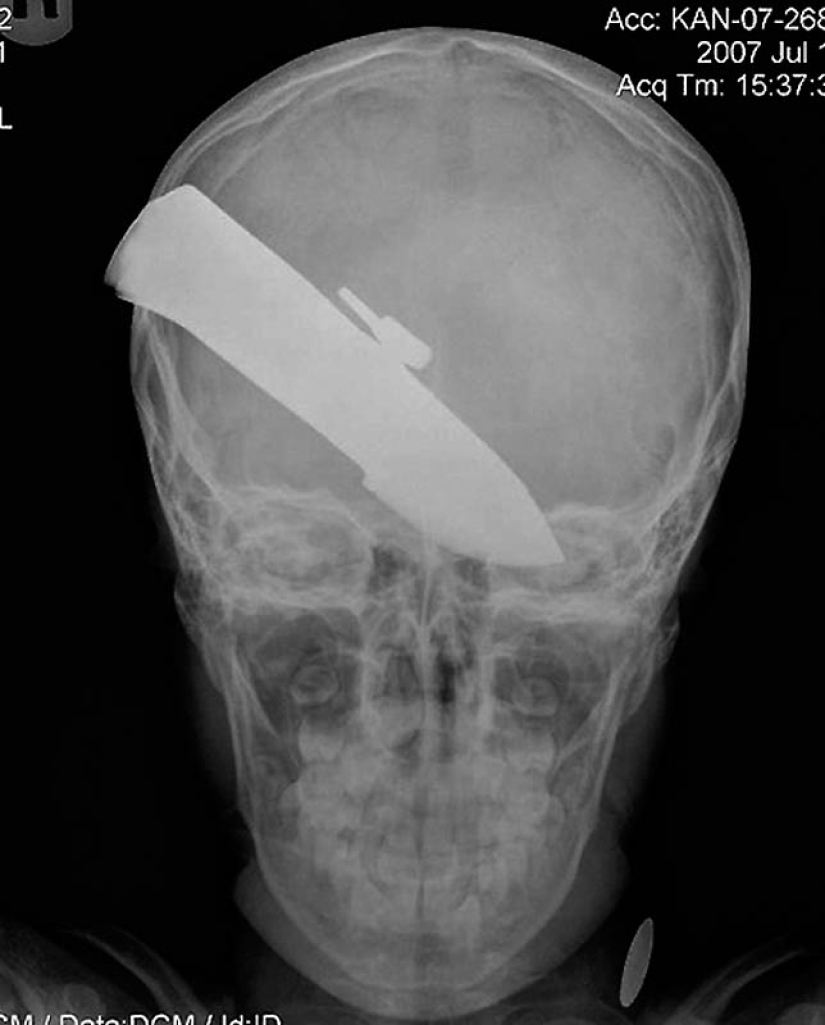

18. a 12-centimeter knife in the skull of a teenager.